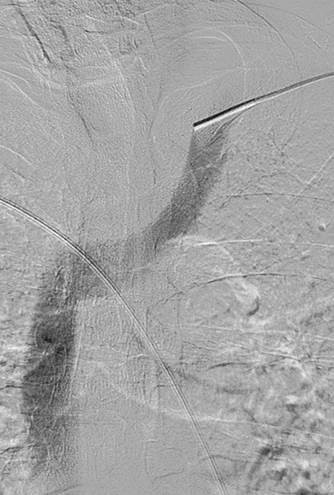

Thrombosed AV graft with stenosis at venous anastomosis.

AngioJet DVX catheter in AV graft.

Imaging post-AngioJet System activation in venous side of AV graft.

Imaging post-AngioJet System activation in arterial side of AV graft.